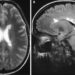

В отличие от EAE, индуцированного PTX, при котором воспалительная демиелинизация в основном ограничивается спинным мозгом, ЭАЭ, индуцированный ЭТХ, вызывает демиелинизацию в мозолистом теле, таламусе, мозжечке, стволе головного мозга и спинном мозге, что больше похоже на распределение нейроанатомических поражений, наблюдаемое при рассеянном склерозе. . Транскрипционные профили эндотелиальных клеток ЦНС выявили ETX-индуцированные гены, которые, как известно, играют роль в преодолении иммунных привилегий ЦНС.